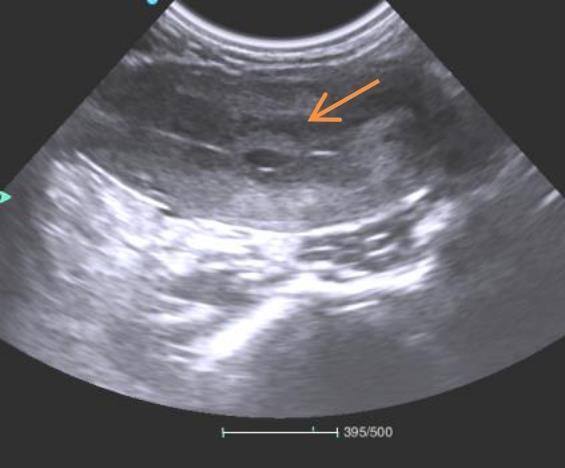

另外,非人灵长类动物的交配行为并不能像家兔和大鼠一样容易被观察到,对于试验过程中它们是否成功交配也成为该类试验开展过程中的技术难点之一。实际操作过程中,在雌猴月经开始后的11~15 d,将雌性和雄性非人灵长类动物1∶1合笼,可设定3 d的交配期,在交配期后的20~25 d进行B超诊断。本机构兽医在食蟹猴妊娠早期,通过B超检查方式发现如图2所示的孕囊结构。可通过观察非人灵长类动物有无明显孕囊来判断其是否妊娠,但这需要经验丰富的临床兽医制定完善的B超检查方法。

图2

妊娠初期雌猴孕囊B超切面

Figure 2

Ultrasound cross-sectional view of gestational sac in a female monkey during early pregnancy